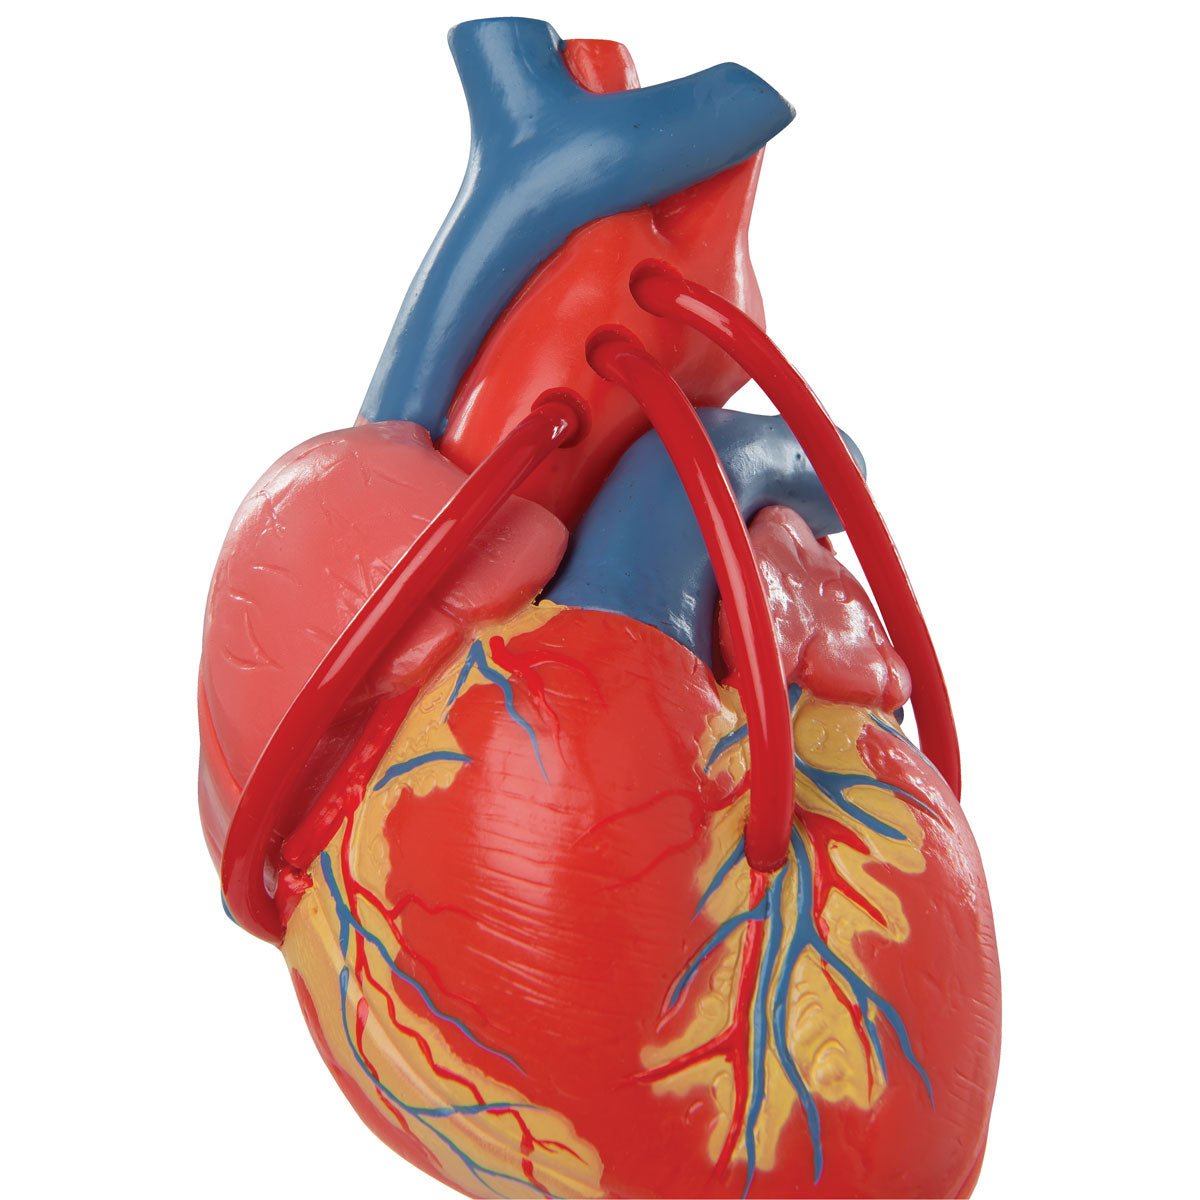

Anatomical models

Selling anatomical models is the mainstay of eAnatomi, although we also spend a lot of resources developing our own anatomical materials such as posters. Anatomical models are used for various purposes and can show both defined tissues, organs and organ systems. Are you looking for a simple model of bone tissue or perhaps an advanced torso model based on MRI technology, you can find it all at eanatomi.com.